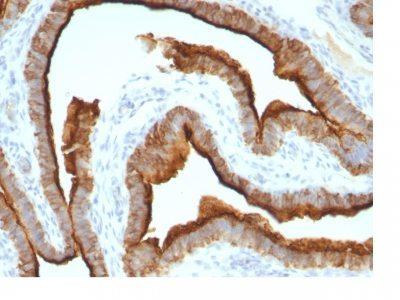

This MAb recognizes full-length MUC1 in a glycosylation-independent manner and can bind to the fully glycosylated protein. The dominant epitope of this MAb is APDTR in the VNTR region. It reacts with the core peptide of the MUC1 protein, which is a member of a family of mucin glycoproteins that are characterized by high carbohydrate content, O-linked oligosaccharides, high molecular weight (>200 kDa) and an amino acid composition rich in serine, threonine, proline and glycine. The core protein contains a domain of 20 amino-acid tandem repeats that functions as multiple epitopes for the MAb. Incomplete glycosylation of some tumor-associated mucins may lead to variable unmasking of the multiple peptide epitopes leading to the observed differences in staining intensity between normal and malignant tissues. This MAb reacts with both normal and malignant epithelia of various tissues including breast and colon.Primary antibodies are available purified, or with a selection of fluorescent CF® Dyes and other labels. CF® Dyes offer exceptional brightness and photostability. Note: Conjugates of blue fluorescent dyes like CF®405S and CF®405M are not recommended for detecting low abundance targets, because blue dyes have lower fluorescence and can give higher non-specific background than other dye colors.

Positive Control

MCF-7 or MDA-231 cells. Breast, colon, ovarian, endometrial carcinoma.

IHC, FFPE (verified), WB (verified)

IHC (FFPE) (verified)|WB (verified)

Immunohistology formalin-paraffin 0.25-0.5 ug/mL|Staining of formalin-fixed tissues requires boiling tissue sections in 10 mM citrate buffer, pH 6.0, for 10-20 min followed by cooling at RT for 20 minutes|Flow Cytometry 0.5-1 ug/million cells/0.1 mL|Immunofluorescence 1-2 ug/mL|Optimal dilution for a specific application should be determined by user